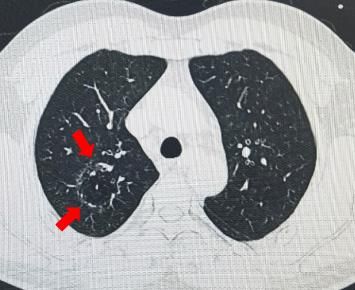

廖先生的胸部CT影像

通过急诊胸部CT检查,医生发现廖先生的肺部长了一个“怪圈”,怀疑这就是导致他咯血的“元凶”。为此,成都三院呼吸与危重症医学科主任李国平带领血管介入团队,就廖先生的病情进行仔细分析,判断这个“怪圈”为肺血管畸形。在李国平的指导下,血管介入团队为廖先生进行支气管动脉造影术,证实患者确实患有比较少见的支气管动脉畸形。